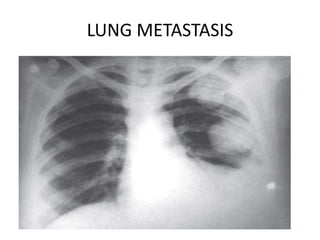

LUNG METASTASIS

– pulmonary- cough, chest pain, hemoptysis, dyspnoea, chest x ray

finding -80%